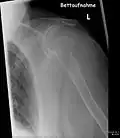

- Vues de fractures pathologiques

Fracture pathologique de l'humérus sur une métastase de carcinome du rein

Fracture pathologique du bras gauche sur une métastase osseuse de cancer du sein

Scintigraphie corps entier avec 99mTc-HDP de la patiente avec une fracture du bras due à une métastase du cancer du sein